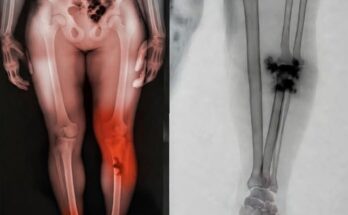

Every 10 years after your 30th birthday, you can lose anywhere from 3% to 5% of your lean muscle. Your bones typically decrease in size and density as you age as well, putting you at a greater risk of suffering from fractures or injuries. (Oh the joys of getting older!) By engaging in active hobbies and exercise, you’re doing yourself a massive favor.